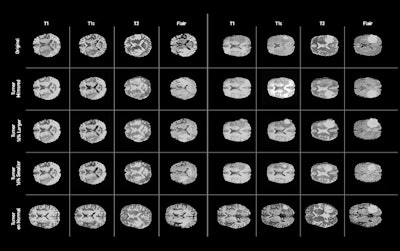

Researchers from NVIDIA, Massachusetts General Hospital and Brigham and Women's Hospital in Boston, and the Mayo Clinic in Rochester, MN, have trained a type of AI algorithm called a generative adversarial network (GAN) to generate synthetic abnormal brain MR images. These synthetic images could be used to augment a small dataset or even on their own to train a deep-learning algorithm, according to Hoo-Chang Shin, PhD, a senior research scientist at NVIDIA.

The algorithm allows developers to alter the size of a tumor on the MR image, change its location, or place it on an otherwise normal brain -- enabling hundreds or even thousands of these synthetic images to be created, according to the researchers. In testing, they found that adding synthetic data to augment real MRI data improved the performance of a deep-learning algorithm.